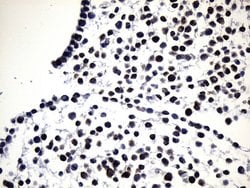

EGFR L858R Mouse anti-Human, Clone: UMAB234, lyophilized, UltraMAB™

EGFR (Epidermal growth factor receptor, HER1, ErbB1) is encoded by the EGFR gene located on chromosome 7 in humans. EGFR belongs to the HER/ERbB family of proteins that includes three other receptor tyrosine kinases, ERbB2, ERbB3, ERbB4. EGFR is a transmembrane receptor and binding of its cognate ligands such as EGF (Epidermal Growth Factor) and TGF alpha (Transforming Growth Factor alpha) to the extracellular domain leads to EGFR dimerization followed by autophosphorylation of the tyrosine residues in the cytoplasmic domain. Phosphorylation of EGFR at certain residues is also mediated by Src-non-receptor kinase. EGFR activation signals multiple downstream signaling cascades such as the Ras - ERK, PI3-K - Akt, Jak - STAT and PKC pathways that help in growth and proliferation of cells. Phosphorylation of EGFR at Y1086 specifically allows binding of the adaptor protein GRB2, leading to activation of the MAPK pathway. Upon receptor activation and signaling, EGFR is endocytosed and targeted for degradation or recycling. Mutations in the EGFR gene are associated with lung cancer and multiple alternatively spliced transcript variants encode different protein isoforms of EGFR have been found. Increased production or activation of EGFR has been associated with poor prognosis in a variety of tumors. Moreover, EGFR overexpression is observed in tumors of the head and neck, brain, bladder, stomach, breast, lung, endometrium, cervix, vulva, ovary, esophagus, stomach and in squamous cell carcinoma. This product is specific for EGFR (mutant L858R).Specifications

| Immunohistochemistry (Paraffin) | |

| Synthetic peptide around the L858R mutation region of the human EGFR conjugated to KLH | |